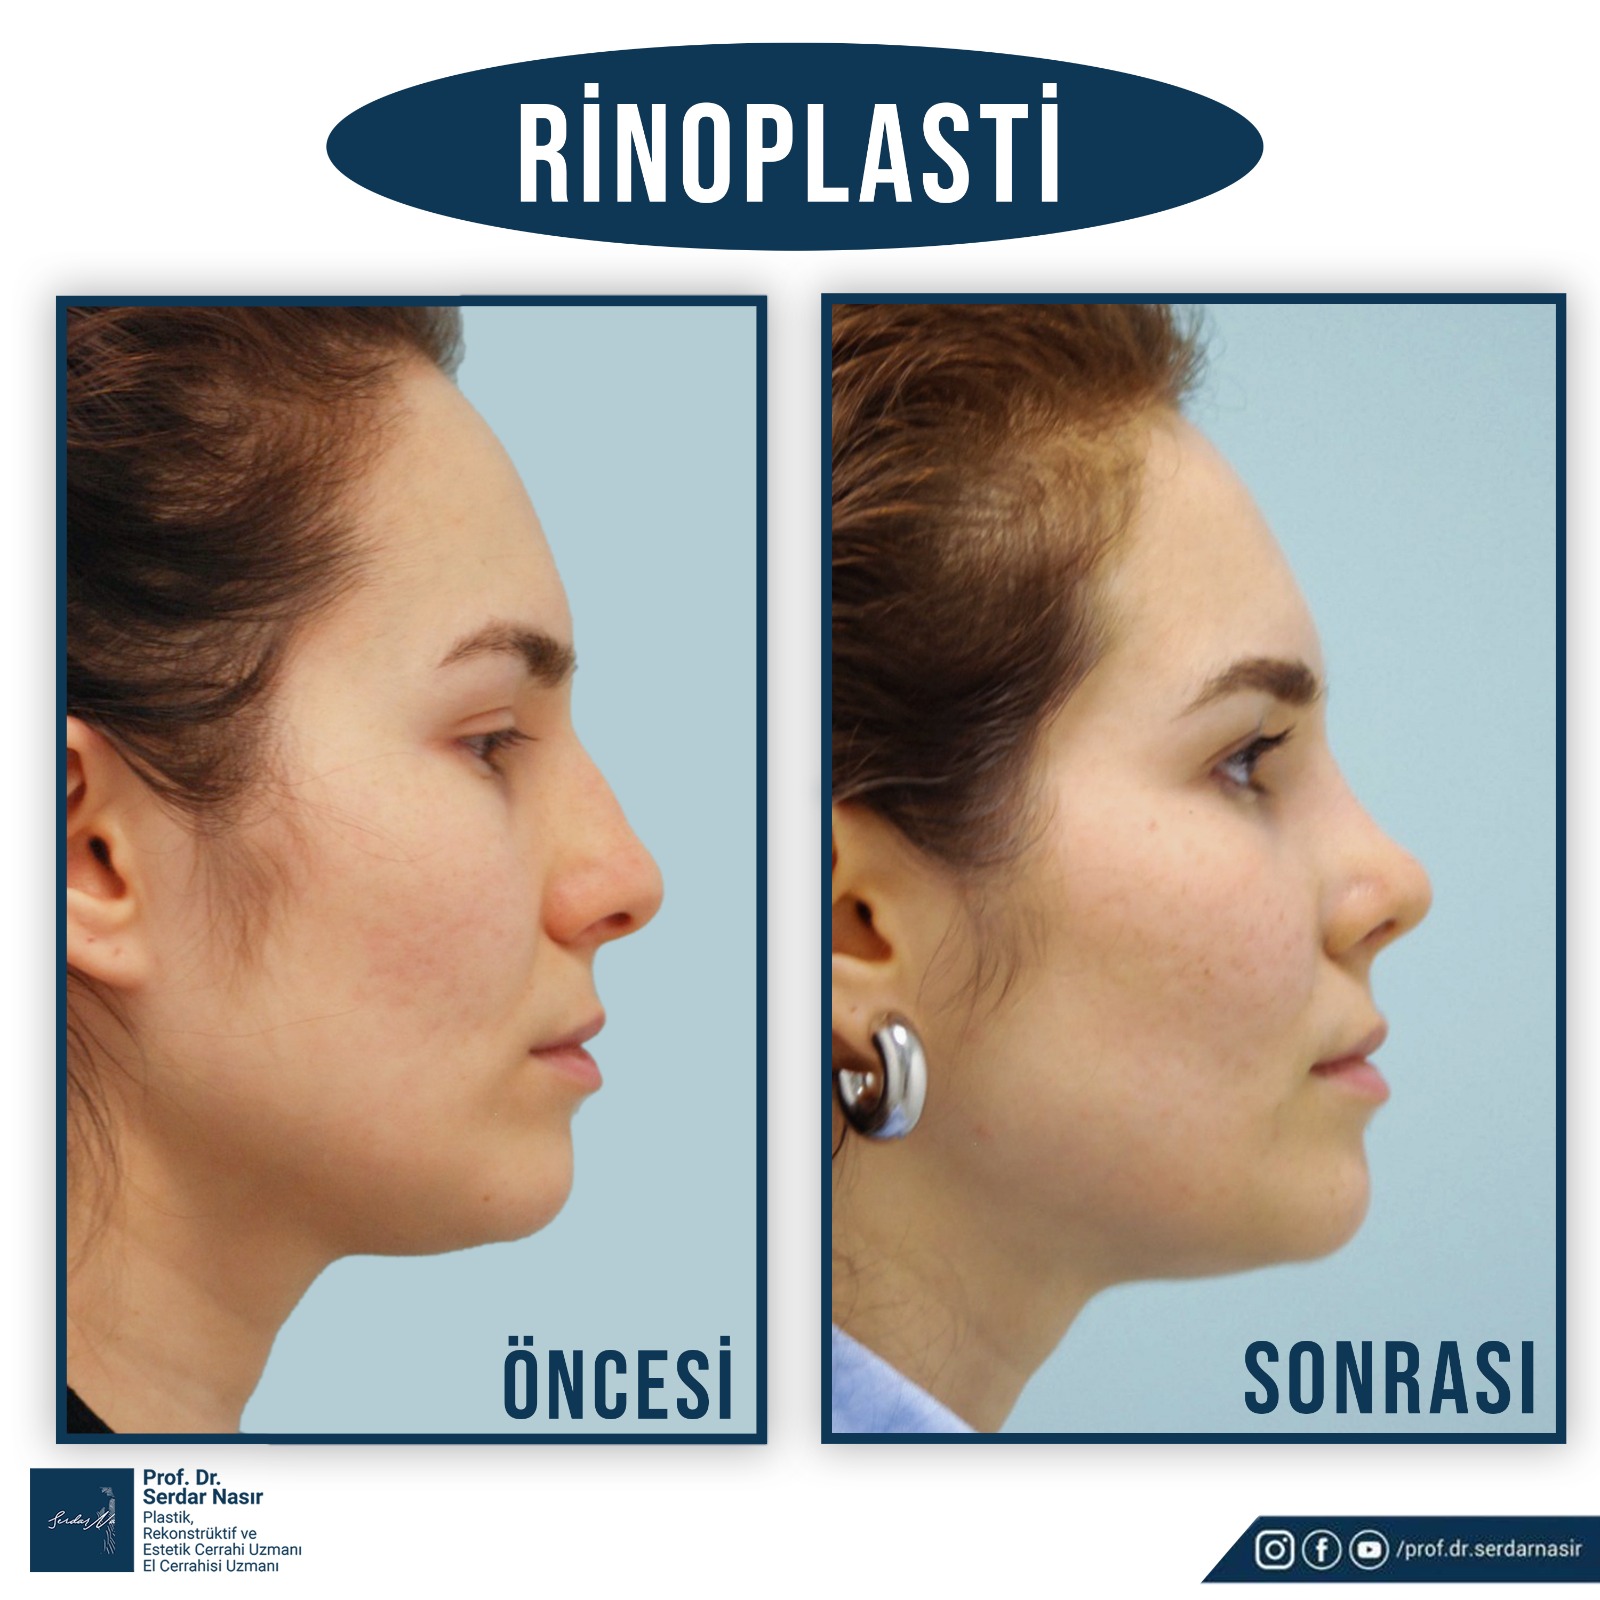

Estetik burun ameliyatı bana göre plastik cerrahinin en zor ameliyatlarından biridir. Çünkü burunda estetik olarak güzel bir sonuç elde etmeye çalışırken aynı zamanda fonksiyonel sonuçta yani hastanın nefes alıp vermesininde bozulmaması ve hatta sorun varsa düzeltilmesi gereklidir. Bu nedenle oldukça dikkatli yapılması gereken ameliyatlardır. Şu da bir gerçektir ki en çok revizyon dediğimiz ilk ameliyattan sonra tekrar bazı küçük deformitelerin veya hoşa gitmen bazı ayrıntıların düzeltilmesinin yapıldığı ikinci ve bazen üçüncü ameliyatlar en çok bu grupta saptanmaktadır. Bu nedenle özellikle ilk ameliyatın başarılı şekilde yapılması bu revizyon olasılığını azaltacaktır. Yine de estetik burun ameliyatı olmayı planlayan bir kişi her zaman için bir revizyon olasılığını akılda tutmasını öneririm.

Burun ameliyatları kapalı veya açık olarak iki teknikle yapılmaktadır. Plastik Cerrahlar hem kendi deneyimleri hemde hastanın ihtiyacına göre bu tekniklerden birini seçmektedir.

Kişisel tecrübeme gelince ameliyat sonrası şişliklerin daha az olması, dokuları daha az travmatize etmesi gibi düşüncelerle ilk planda kapalı tekniği tercih etmekteyim. Ancak hastanın burun deformitesi özellikle burun ucuna yönelik ağırlıktaysa veya çok detaylı bir cerrahi girişim yapılacaksa açık tekniği tercih etmekteyim. Ancak tecrübelerime göre kapalı teknik ile açık tekniğe gerek kalmadan bir çok hastanın sorunu çözülebilmektedir.